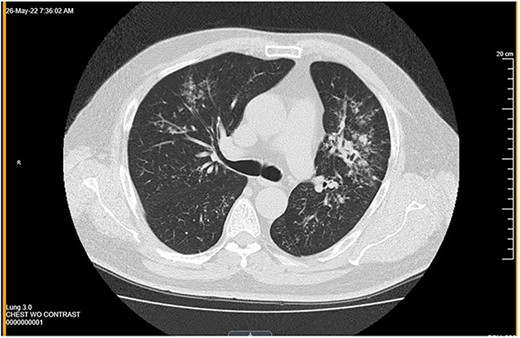

Neck ultrasound demonstrated an enlarged right-sided with a nodule (measuring 3.58 × 4.12 cm) and two left-sided nodules measuring 1.1 and 1.4 cm in size (Fig. 1a and b). The ultrasound also showed a 1 cm nodule inferior to the left lobe, suspicious of a parathyroid adenoma or enlarged lymph node. CT chest revealed multiple nodules in the left pulmonary parenchyma (Fig. 2). Flexible laryngoscopy revealed normal bilateral vocal cord movement but severe inflammation and swelling of the larynx. Subsequent FNA of both the right and left thyroid nodules showed benign results.

Computed tomography showed multiple nodules in the left pulmonary parenchyma.

The patient underwent an uncomplicated thyroidectomy. Histopathologic examination demonstrated a thyroid (108 grams) with nodular and hyperplastic thyroid follicles. Several small nodules in the right lobe consisted of caseating and noncaseating granulomas (Fig. 3a) with spherules (10–40 μm) characteristic of Coccidioides immitis (Fig. 3b and c). No neoplasm was present in any of the tissue. Pathology was negative for acid-fast stain for Mycobacterium. Subsequent CT of the chest showed extensive bilateral miliary nodules. The patient was started on oral fluconazole therapy at 400 mg/d.